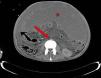

Varón de 23 años, con cirrosis secundaria a hepatitis de células gigantes del adulto. Tras un episodio de shock séptico por peritonitis bacteriana, sufre parada cardiorrespiratoria, presenta distensión abdominal y hemoglobina 3,9 g/dl. La tomografía computarizada (fig. 1) muestra ascitis masiva hiperdensa (ver asterisco), colapso de la vena cava inferior y de la aorta, que es filiforme (ver flecha) y (fig. 2) desaparece a la altura de las ilíacas (ver flechas), sin fuga de contraste. Se realiza paracentesis, aspirando sangre. El paciente fallece por shock refractario. El cuadro es un hemoperitoneo espontáneo por sangrado de varices intraabdominales. El colapso de aorta, la vena cava inferior y la hipodensidad inicial del bazo son signos radiológicos de shock hipovolémico.